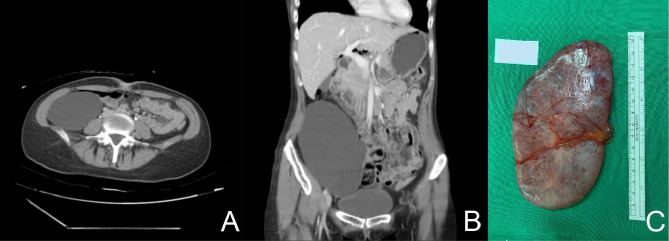

Case presentation: We report a case of a 32-year-old woman who was incidentally diagnosed with a right retroperitoneal cyst during routine prenatal ultrasonography. The patient remained asymptomatic until postpartum, prompting further evaluation of the cyst. Imaging studies identified a large cystic mass, ultimately leading to diagnostic laparoscopy and surgical excision. Histopathological analysis confirmed the diagnosis of a mucinous cystadenoma with neuroendocrine cell proliferation.